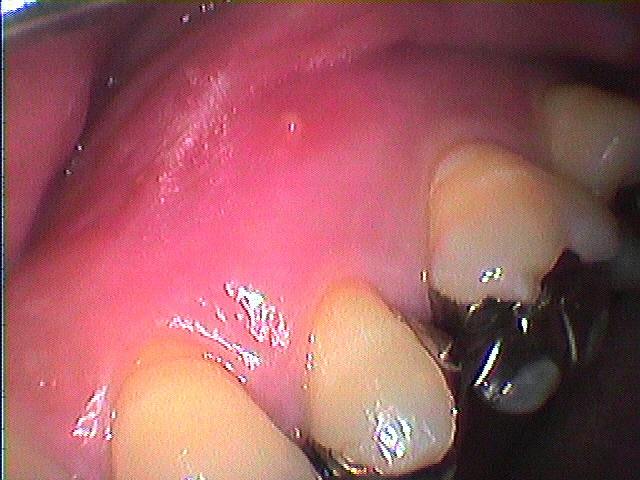

頬側を開け、病巣をソウハを行い骨補填剤を入れることになりました

補填剤をつめた直後のレントゲン

かなり6番寄りにまで病巣が波及し、

根の治療では確かに治りにくくなっていました